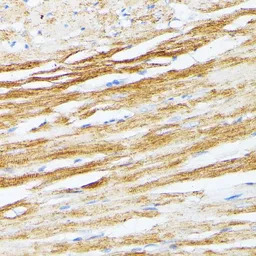

IHC-P analysis of rat heart tissue using GTX16425 Tropomyosin 2 antibody.

Dilution : 1:100